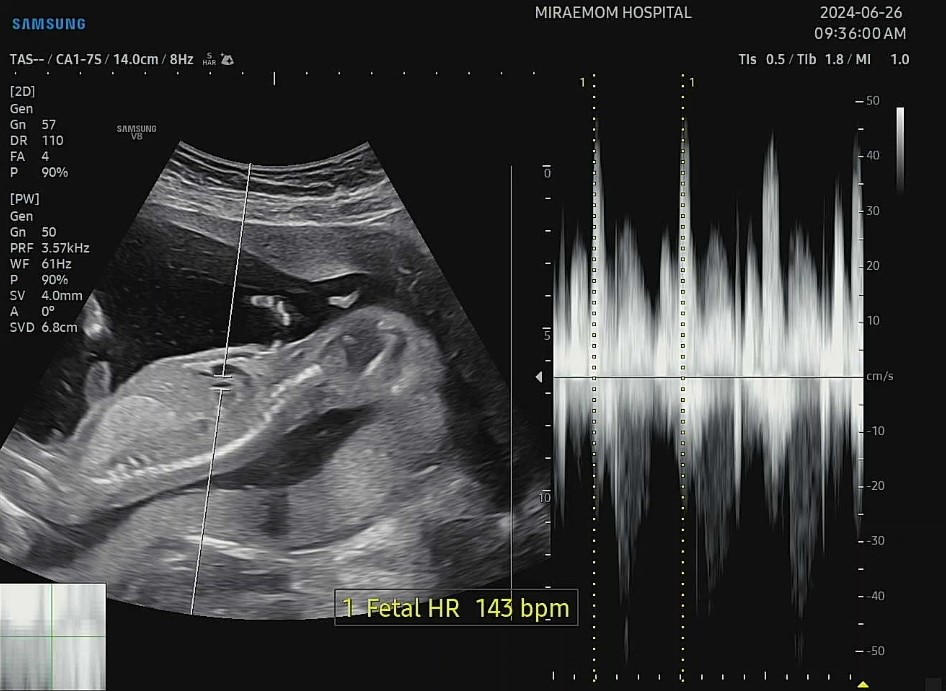

그래도 두 아이 모두 아주 잘뛰고 있는 심장소리에 마음은 놓였답니다^^*

엄마는 죽을것같은데 너무 잘 있는 우리 아들둥이들~ 볼때마다 사랑스러워요ㅎㅎ